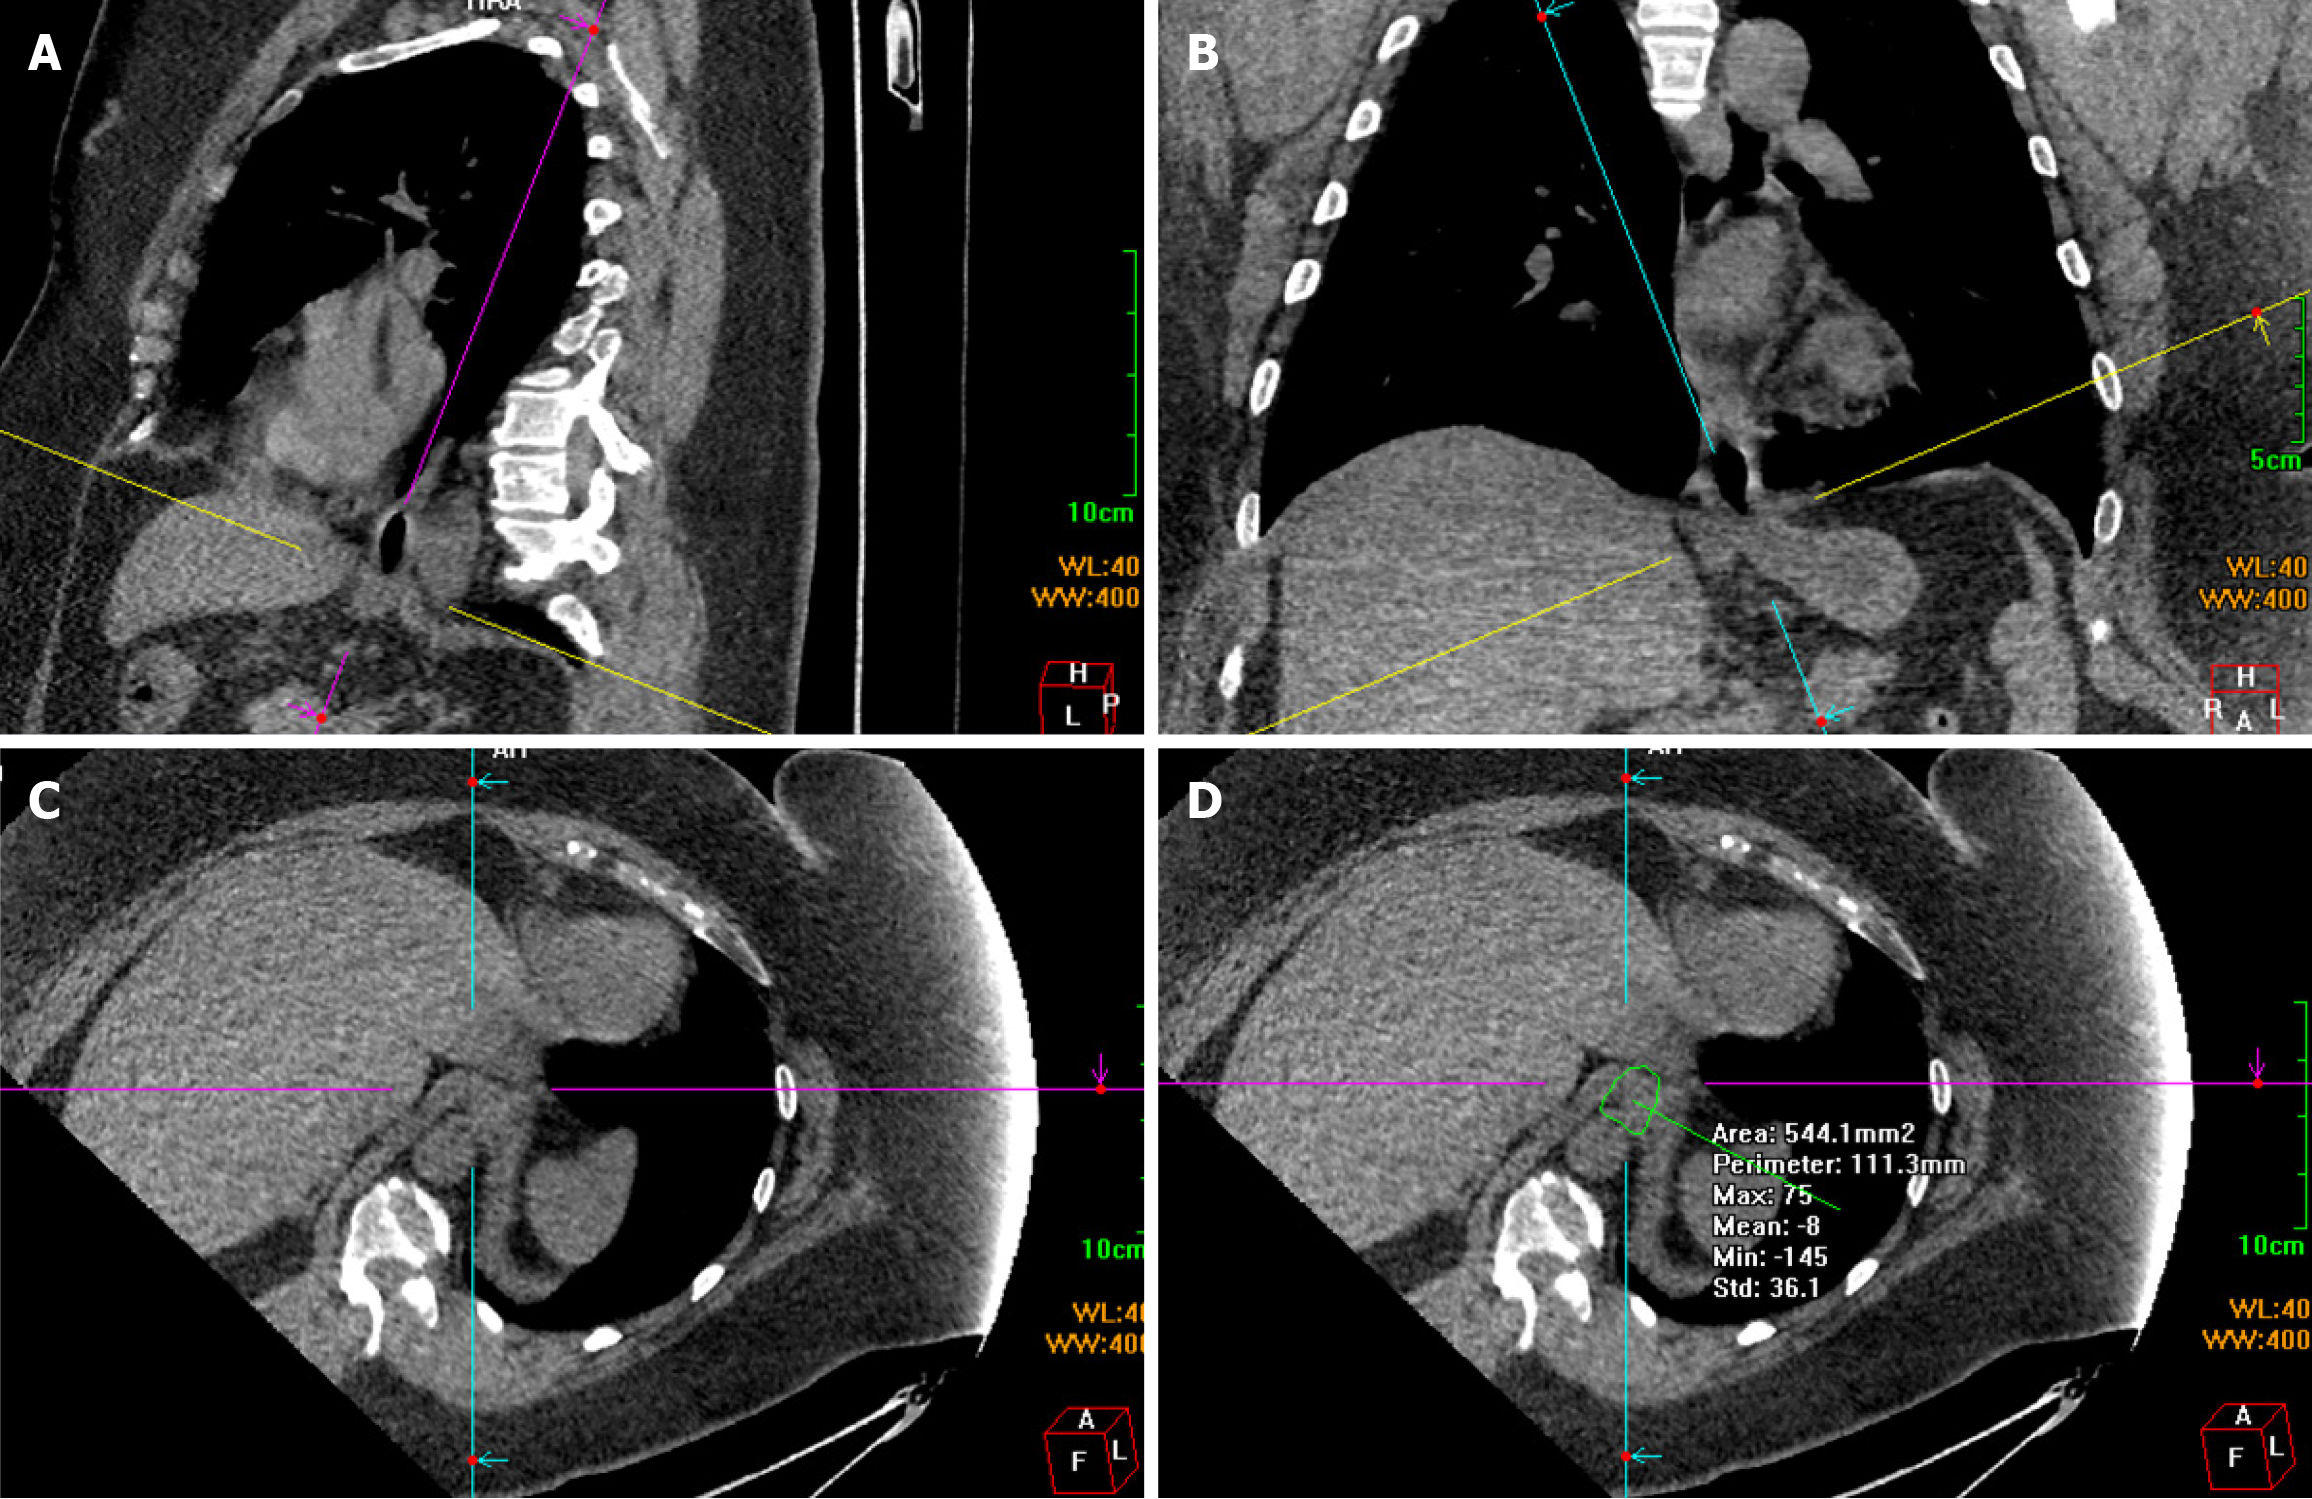

Chest and abdominal CT scans were performed using a 64-slice spiral CT scanner (Discovery CT750 HD; GE Medical Systems, Waukesha, WI, United States) covering the distal esophagus, diaphragm, and proximal stomach. Scanning was performed at a tube voltage of 120 kV, tube current of 70-260 mA, field of view of 50 cm, 521 × 512 matrix, and slice thickness of 5 mm. Scanning was enhanced with an intravenous bolus injection of 100 mL of the non-ionic contrast agent iohexol at 2.5-3.5 mL/second. The raw scan data were transmitted to a workstation for MPR with a slice thickness of 5 mm. The entire circumference of the esophageal hiatus was revealed using the double-oblique correction plane technique[5]. First, a slice passing through the center of the esophageal hiatus was identified in the sagittal plane. The line representing the axial plane was moved and rotated to intersect the anterior and posterior margins of the esophageal hiatus. This line generally slopes toward the spine. Consequently, the line representing the oblique coronal plane was approximately parallel to the distal esophagus (Figure 1A). The sagittal diameter was obtained by measuring the distance between the anterior and posterior margins. The line representing the axial plane was then moved and rotated on the coronal plane to intersect the left and right margins of the esophageal hiatus. This line generally tilted downward toward the right (Figure 1B). The distance between the left and right margins was measured to obtain the transverse diameter. The resulting double oblique axis plane was the esophageal hiatus plane (Figure 1C). The angle and position were slightly adjusted to maximize the hiatal margins. Finally, a polygonal tool was used to manually define the inner margins of the hiatus, and the cross-sectional area of the esophageal hiatus was measured (Figure 1D). Three researchers performed the measurements independently.